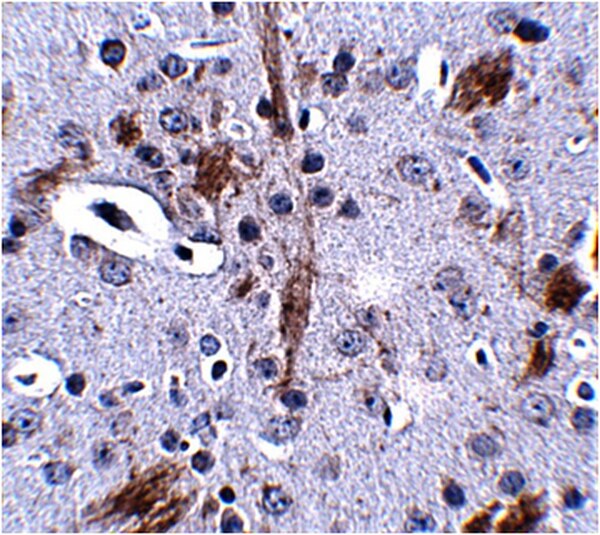

Application NotesImmunohistochemistry Analysis: 2.5 µg/mL of this antibody from a representative lot detected. TTBK1 in mouse brain tissue.